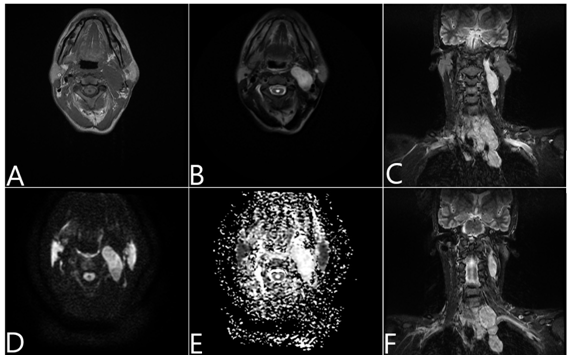

Figure 2 MRI findings: (A) In the T1-weighted sequence it presented low signal. (B) In the T2-weighted sequence presented high signal. (D/E) Diffusion weighted imaging (DWI) and apparent diffusion coefficient (ADC), without evidence of diffusion restriction. (C/F) Coronal T2 STIR showing all involvement of the vagus nerve from the pars vascularis of the jugular foramen extending to the superior mediastinum and returning to the recurrent laryngeal nerve.

The first description of a parapharyngeal schwannoma case occurred in 1933 by Figi.5,6  Since then, there have been few reports of cases with giant mass presentations. In this case, GVS is an extremely rare entity, so the understanding the anatomy, epidemiology, clinical presentation, imaging, and histologic findings can make the difference.7 In anatomy, it should be emphasized that the vagus nerve runs within the carotid between the internal or common carotid artery, and the internal jugular vein as a neurovascular bundle, traveling towards the neck, chest, and abdomen.4,8 In the case presented, it is interesting to observe the involvement of the recurrent laryngeal nerve, which was determinant for the obstruction of the airways. Preoperative diagnostic exams include CT, MRI, and biopsy.4,7 CT is important for discarding bone lesions, delimiting anatomical spaces, and assessing the extent of the lesion. But MRI can lead to diagnostic suspicion in the preoperative period, considering the well circumscribed mass located between the internal jugular vein and the carotid artery. Not presenting anomalous enhancement or restriction to the diffusion.3 As the histological pattern, malignant schwannoma tumors differ from the benign type in their higher mitotic rate, presence of necrosis and infiltrative appearance, in addition to irregular positivity for the S-100 protein. In our case, the results were very typical.7 In short, knowledge of the anatomy and path of the vagus with its recurrences are essentials, as well as understanding the behavior of slow-growing tumors of head and neck is the key for this diagnosis.